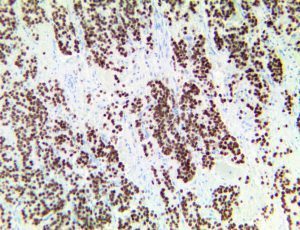

It is the ICU physician who is most likely to witness one of the deadliest manifestations of the abnormal immunological response, the cytokine storm syndrome (CSS). This response is also referred to by some as the cytokine release syndrome (CRS). CSS is characterized by continuous activation and expansion of macrophage and lymphocyte populations, which secrete large amounts of cytokines, causing the cytokine storm. This massive cytokine release is akin to hemophagocytic lymphohistiocytosis (HLH) disease, a syndrome characterized by initial unchecked and persistent activation of cytotoxic T lymphocytes and NK cells.

Clinical and laboratory manifestations of HLH include fever, enlarged liver and/or spleen, neurologic dysfunction, coagulopathy, liver dysfunction, cytopenias (i.e., low levels of erythrocytes, leukocytes, and/or platelets), hypertriglyceridemia, hyperferritinemia, hemophagocytosis, and eventually diminished NK cell activity as the immune system becomes progressively paralyzed. HLH can be familial (primary HLH) or secondary to another disease process (sHLH), such as rheumatic disease, in which it is referred to as macrophage activation syndrome (MAS, characterized by elevated ferritin).